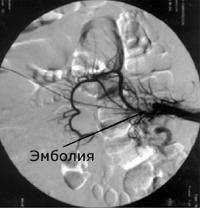

При обзорной рентгенографии брюшной полости определяется пневматизация кишечника, наличие горизонтальных уровней жидкости в брюшной полости. Специфическим методом диагностики острой окклюзии мезентериальных сосудов является селективная мезентерикография, которая уже на ранней стадии заболевания может выявить отсутствие кровотока в стволе и ветвях брыжеечной артерии. При наличии технической возможности выполняется магнитно-резонансная ангиография мезентериальных сосудов.